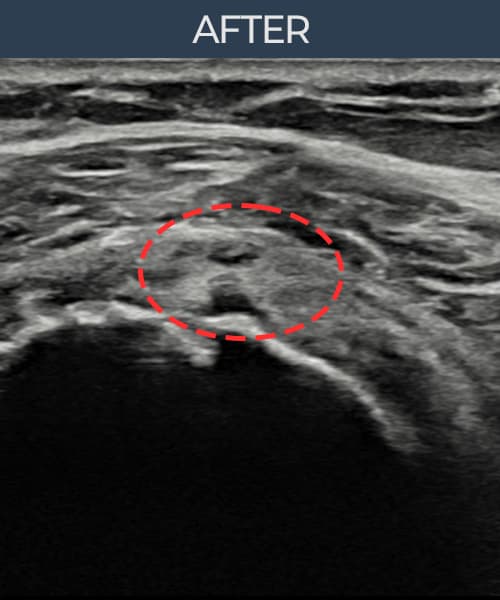

超音波検査にて腱板 部分断裂(6mm × 3mm (腱厚の約35%欠損))を確認。縫縮術施行後、腱の連続性が回復し、日常生活に復帰されました。

施術後

術前超音波にて腱板 部分断裂・肩棘上筋腱のエコー不連続と腱欠損(6mm × 3mm (腱厚の約35%欠損))を確認。術後超音波では断裂部位が再生組織で充填され、腱の連続性回復とエコーパターンの正常化が確認されました。

持続する肩痛で来院された患者様です。超音波検査にて腱板 部分断裂(欠損:6mm × 3mm (腱厚の約35%欠損))を確認し、超音波ガイド下で非手術的縫縮術を施行しました。術後は約4〜6週間のブレース装着の後、段階的なリハビリプログラムを実施。経過超音波で腱の連続性回復を確認し、患者様は無事に日常生活へ復帰されました。